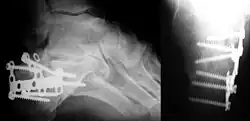

Im Wesentlichen muss die Entscheidung getroffen werden, ob eine konservative Frakturbehandlung z. B. durch eine Gipsruhigstellung oder eine operative Behandlung erfolgt. Zur konservativen Behandlung zählt auch die geschlossene Reposition einer Fehlstellung unter Narkose mit anschließendem Gips. Bei operativem Vorgehen erfolgt meist eine offene Reposition der Knochenbruchteile und deren anschließende Fixierung durch eine Osteosynthese („ORIF“ – open reduction and internal fixation). Generell empfiehlt sich eine operative Korrektur bei mehreren Fragmenten, nicht geschlossen reponierbaren Frakturen, bei anhaltenden Instabilitäten, bei Frakturen, die ins Gelenk reichen. Eine absolute OP-Indikation besteht bei Vorliegen eines arteriellen Verschlusses, einer Nervenverletzung oder eines Kompartmentsyndroms. Auch bei offenen Frakturen erfolgt meist eine Operation, um ein Débridement durchführen zu können und weil durch eine sichere Stabilisierung die Gefahr einer späteren Infektion vermindert wird. Bei großen Defekten müssen oft auch mehrere Wiederholungseingriffe zur Sanierung und zum Débridement erfolgen.